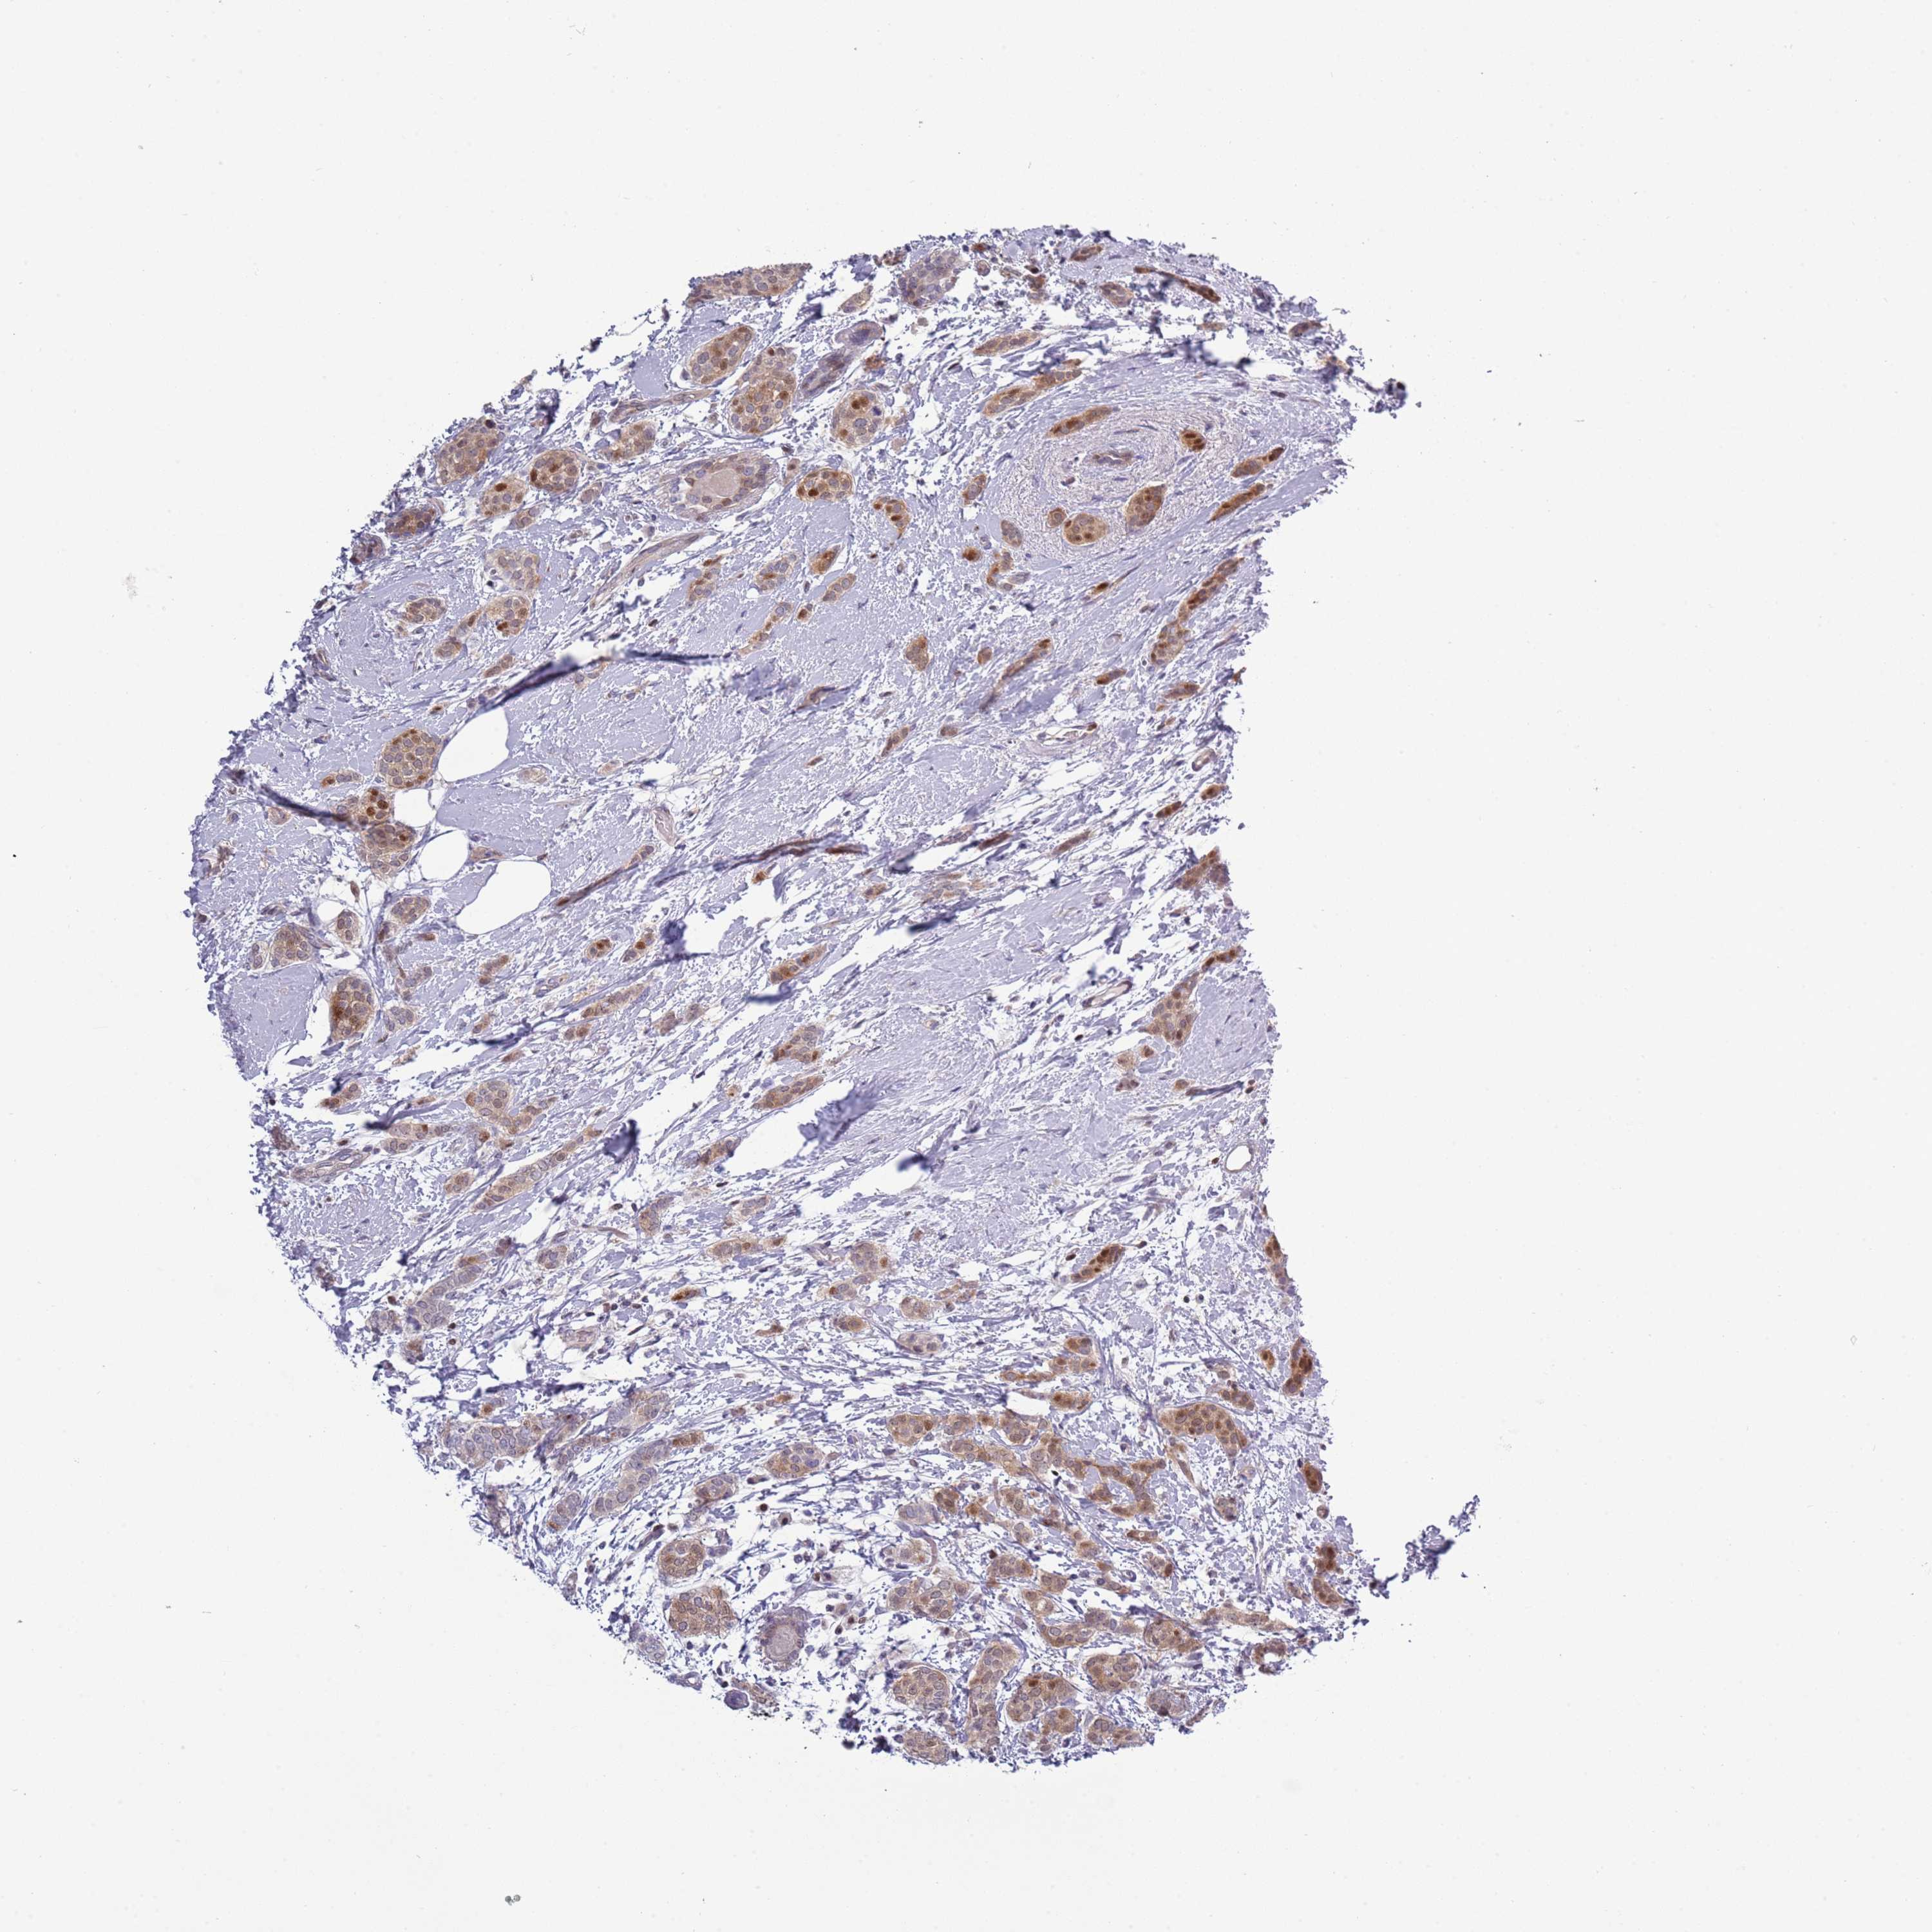

CANCER BREAST CANCER Show tissue menu

BRCA TCGA BRCA VALIDATION PROTEIN EXPRESSION